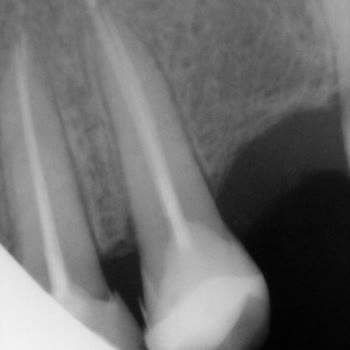

21.02.2024 tarihinde diş ağrısıyla kliniğe başvurdum ve kanal tedavisi olmam gerektiği belirtildi. İşlemlere başlandı. İlk olarak klasik bir şekilde dişin içerisine ilaç koyup beni gönderdiler ve bir hafta sonrası için randevu verdiler. Bu süreç içerisinde ağrılarım azalmadı. İkinci randevuma gittiğ...